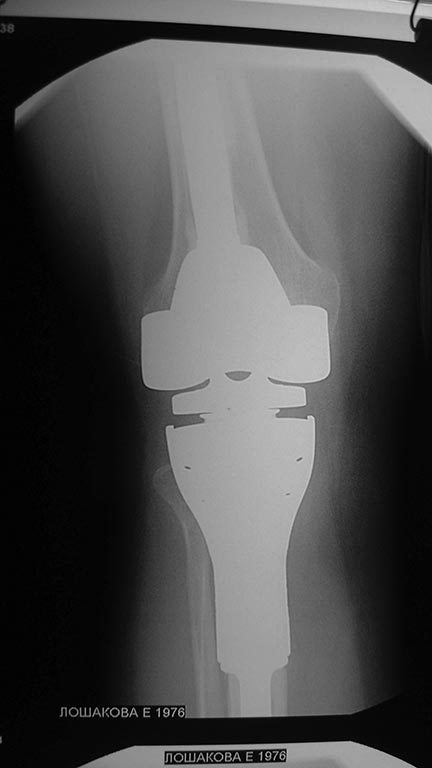

Уважаемые коллеги помогите с дальнейшей тактикой лечения.Больная 1976 г.р оперирована в октябре 2012 по поводу остеобластокластомы проксимального метафиза пр.большеберцовой кости модульным имплантом stryker

послеоперационное течение гладкое.Ходит с полной нагрузкой.Незначительно прихрамывая на пр.ногу .П/о рубец до 20 см без признаков воспаления Пальпаторно по передней поверхности метаэпифиза ю/берцовой кости .Активного разгибания нет ,и собственная связка надколенника не контурирует.Пассивные движения в полном обьеме.На контрольных рентгенограммах признаков нестабильности нет.В течении последних трех недель появилось по передней поверхности пр.голени серома.Пунктирована несколько раз – прозрачная синовиальная жидкость.Взята на посев –чуствительна к гентомицину,цефазолину ,цефтриаксону и левофлоксацину.В настоящее время получает цефазолин 1.0 в/м 3 раза и гентомицин 160 мг в/м 1 раз.(уже 5 дней)Динамики нет, жидкость продолжает скапливаться примерно в том же обьёме.